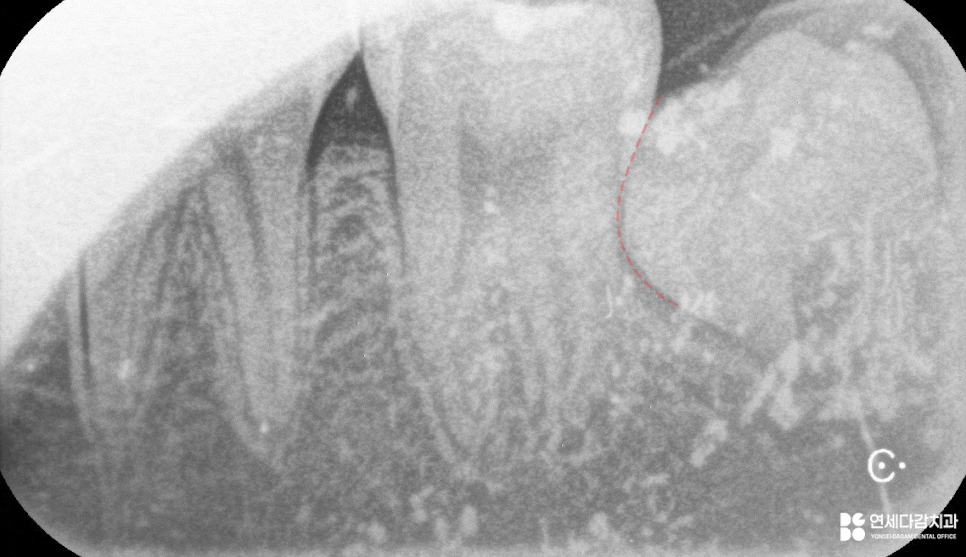

다만 앞서 수립한 계획 속에서도

치관의 크기가 지나치게 크거나 단단하면

치조골 손상이나 치근 파절의 위험성이 높습니다.

이럴 때는 안전을 위해서라도

치관을 분할하는 방법을 고려할 수 있습니다.

가락동 치과 에서 설명하는

이 방식은 뼈를 과도하게 삭제하지 않고,

주변 연조직과 신경관에 전달되는

자극을 최소화할 수 있습니다.

이 과정에서 치배 조직이 함께 확인되는 경우

가능한 제거와 동시에 병리학적 검사를

의뢰하는 것도 바람직합니다.

치배는 대부분 생리적인 조직 중 하나이지만,

드물게는 치성 낭종이나 악성 종양이 될 수 있으니

의심 소견이 있는 경우 분석을 병행하는 것도

안전하고 책임감 있는 진료 과정이라 할 수 있습니다.

가락동 치과 에서 확인해 본 결과

과형성된 치배로 결론이 나왔으며,

해당 부위에 대한 소독과 경과 관찰에 따라

교정 치료는 원활하게 받을 수 있습니다.